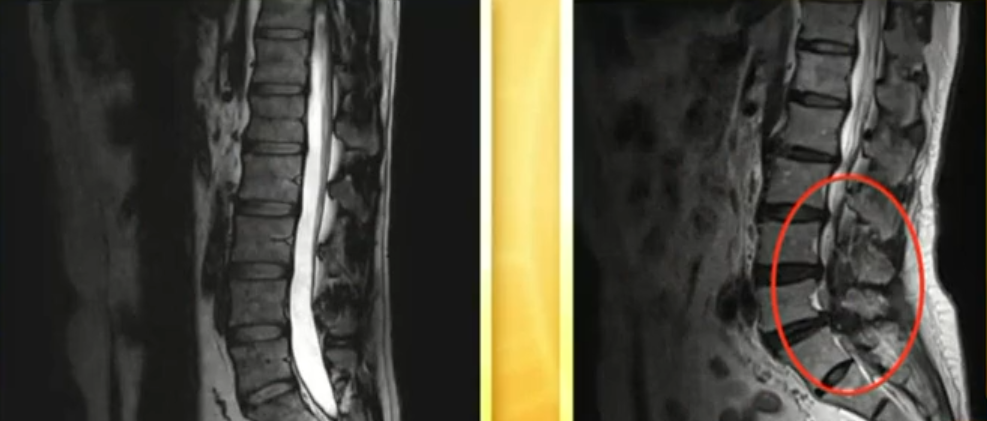

工作时无意中撞门上

被疼痛折磨整整两年